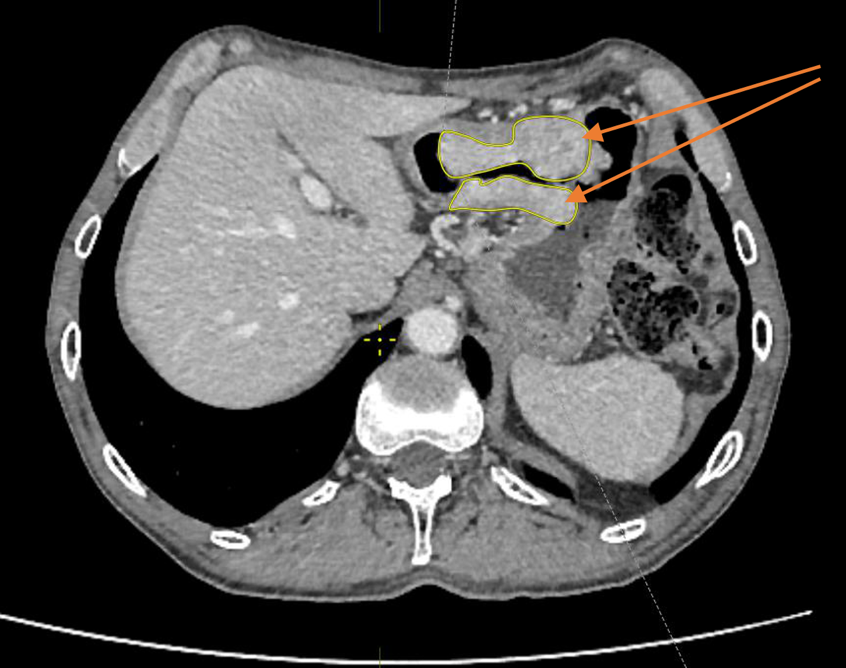

Материал и методы. Представлено 3 клинических случая одновременного развития плоскоклеточного рака пищевода и аденокарциномы желудка у пациентов, получавших лечение в ГУЗ «Областной клинический онкологический диспансер», г. Ульяновск, и ГАУЗ СО «Свердловский областной онкологический диспансер», г. Екатеринбург. Пациентам проведены хирургическое вмешательство, химиотерапия и лучевая терапия.

Результаты. Первично-множественный синхронный плоскоклеточный рак пищевода и аденокарцинома желудка представляют собой сложную клиническую задачу, требующую вмешательства мультидисциплинарной команды специалистов. Химиолучевая терапия с использованием схемы FOLFOX продемонстрировала хорошую переносимость и позволила достичь удовлетворительного клинического ответа со стороны опухолей обеих локализаций.